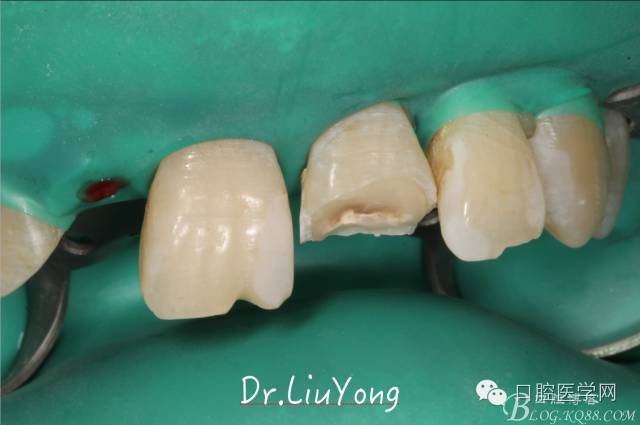

由于上前牙外傷后未及時行松牙固定,已拖延1月,因此先行松牙固定,嘗試保留。因A2冠根折,牙冠缺失,故行A1-B3松牙固定,選擇鄰面樹脂粘結(jié)固定,因為牙齦極易出血,因此選擇橡皮障下用流體樹脂進行松牙固定。同時A2B1根管治療。

手術(shù)后1月,決定先行臨時修復(fù),由于患者為重度深覆合,因此考慮將上前牙通過臨時修復(fù)體,降低切端的高度,減輕覆合,同時將舌傾的牙冠形態(tài)調(diào)整為較為直立。B2為根折到齦下1.5mm,考慮到患者無法接受正畸,同時如果近中鄰面行冠延長手術(shù)會帶來后續(xù)的黑三角美觀問題,因此選擇在橡皮障下行齦壁提升,然后A2纖維樁+樹脂核,A1-B2臨時樹脂貼面修復(fù),A2臨時冠修復(fù)。